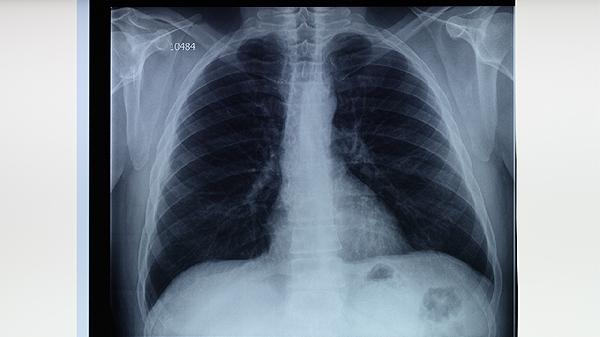

肺结核患者可遵医嘱使用异烟肼片、利福平胶囊、吡嗪酰胺片、乙胺丁醇片、链霉素注射液等抗结核药物。肺结核是由结核分枝杆菌感染引起的慢性传染病,需规范联合用药以减少耐药性,具体用药方案需由医生根据病情制定。

肺结核患者除规范用药外,需保持充足营养摄入,每日保证优质蛋白如鸡蛋、鱼肉及新鲜蔬菜水果。注意居室通风消毒,咳嗽喷嚏时掩住口鼻,痰液需焚烧处理。治疗期间避免劳累,保证8小时睡眠,戒烟限酒。严格遵医嘱完成6-8个月全程治疗,即使症状消失也不可自行停药,定期复查胸部影像学和痰菌检测。出现药物不良反应应及时就医调整方案,耐药结核患者需进行药物敏感性试验指导用药。